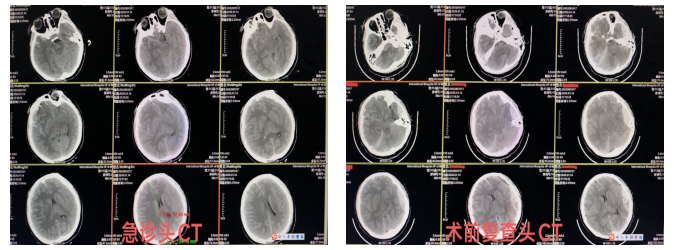

患者孙某某因车祸致颅脑外伤意识不清1小时后送至我院急诊科。入院时患者已呈昏迷状态,急诊CT提示右侧额颞顶枕部急性硬膜下血肿、广泛脑挫裂伤、蛛网膜下腔出血,中线结构移位明显,大脑镰疝形成,右锁骨骨折,右侧第5肋骨骨折。

急诊科董海涛主任医师紧急完善相关术前检查,并请骨科、胸外科、神经外科等多学科会诊后收住神经外科,拟急诊行颅内血肿去骨瓣减压术,术前备皮过程中发现患者右侧瞳孔散大固定,紧急输注甘露醇125ml并急复查头部CT,提示左侧颞顶部新发硬膜外血肿。

手术开始前查体患者双侧瞳孔均已散大,对光反射消失,经与患者家属沟通后行右侧额颞顶部硬膜下血肿清除去骨瓣减压术+颅内压探头置入术+左侧颞顶部硬脑膜外血肿清除术。